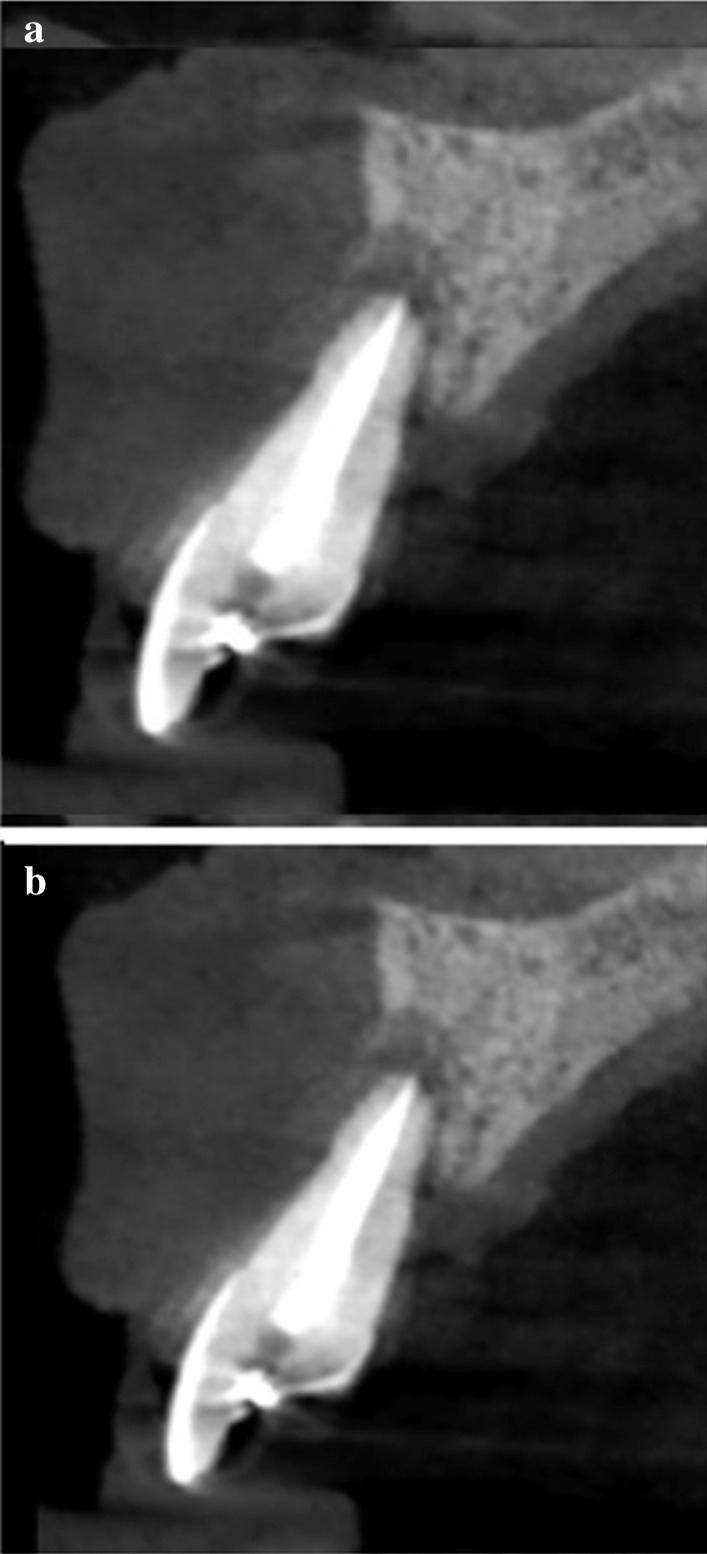

A total of 9 teeth were extracted from 5 patients. The extracted teeth were prepared immediately with the Bonmaker device. The extraction sockets were filled up with ATB powder. Six months after extraction, standardized intraoral x-rays and CBCT scans were performed. Re-entry was performed under local anaesthesia. Core biopsies were harvested for histological analysis and implants were placed.

从 5 名患者中总共拔出 9 颗牙齿。用 Bonmaker 设备立即对拔出的牙齿进行准备。用 ATB 粉末填充拔牙窝。拔牙后 6 个月,进行标准化的口腔内 X 光和 CBCT 扫描。在局部麻醉下进行再进入。采集核心活检进行组织学分析并植入种植体。